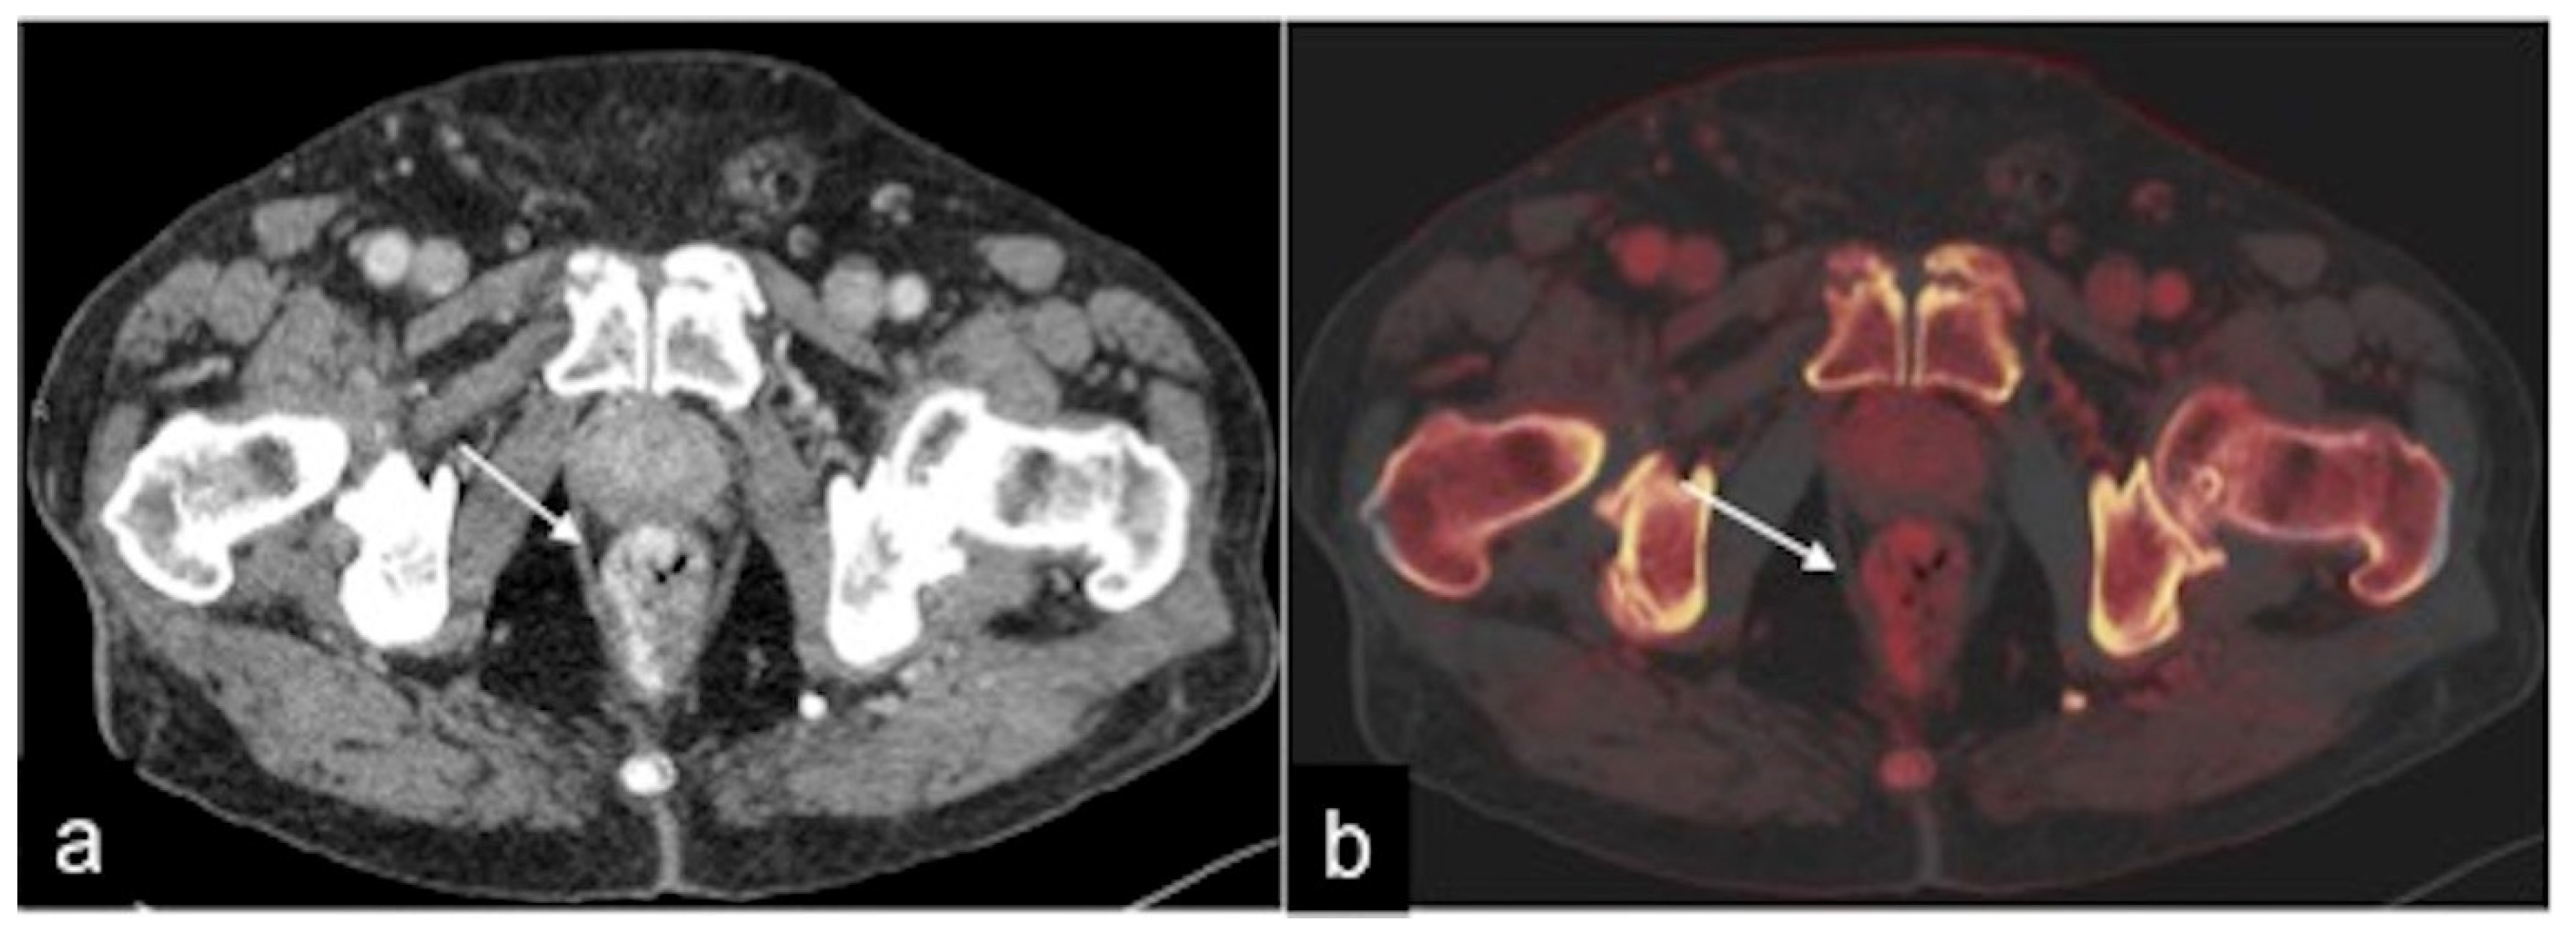

2.4. Dual-Energy CTA (DECTA)

- Trabzonlu, T.A.; Mozaffary, A.; Kim, D.; Yaghmai, V. Dual-energy CT evaluation of gastrointestinal bleeding. Abdom. Radiol. 2020, 45, 1–14. [Google Scholar] [CrossRef] [PubMed]

| DECTA post-processing | 40–60 keV (i.e., virtual monoenergetic), iodine density, virtual non-contrast and standard mixed series | 40–60 keV (i.e., virtual monoenergetic), iodine density, virtual non-contrast and standard mixed series |